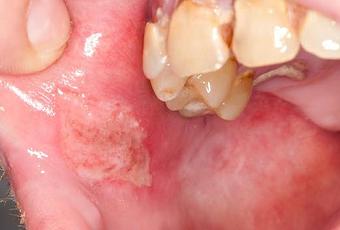

Los sitios más comunes de la inflamación incluyen:Las úlceras de boca y las úlceras genitales son generalmente dolorosas y pueden variar en tamaño de unos pocos milímetros a 2 cm. Las úlceras en la boca se producen en las encías, la lengua y el revestimiento interior de la boca. Las úlceras genitales ocurren en el escroto y el pene de los machos y la vulva de las mujeres. Ambos tipos pueden dejar cicatrices.